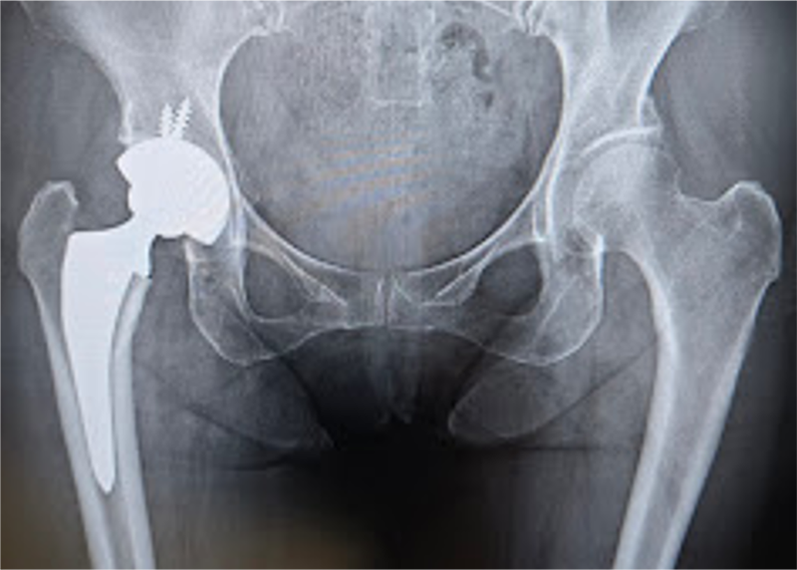

〈手術後のレントゲン〉(正面)